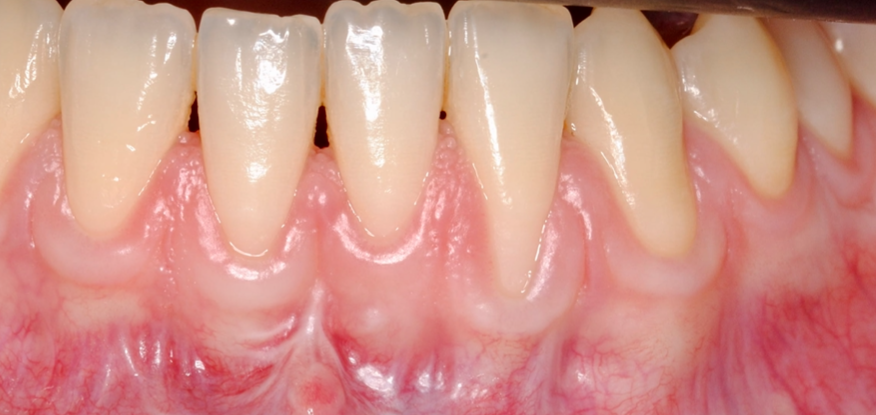

Os enseñamos este nuevo caso el Dr. Arturo Sánchez Colodro en nuestra clínica dental de Jaén, nos muestra un caso donde se puede apreciar con mucha claridad el antes y después de un caso de recesiones inferiores. Este caso ha sido tratado con la última y más avanzada tecnología en digitalización dental.

Fotografías del proceso: